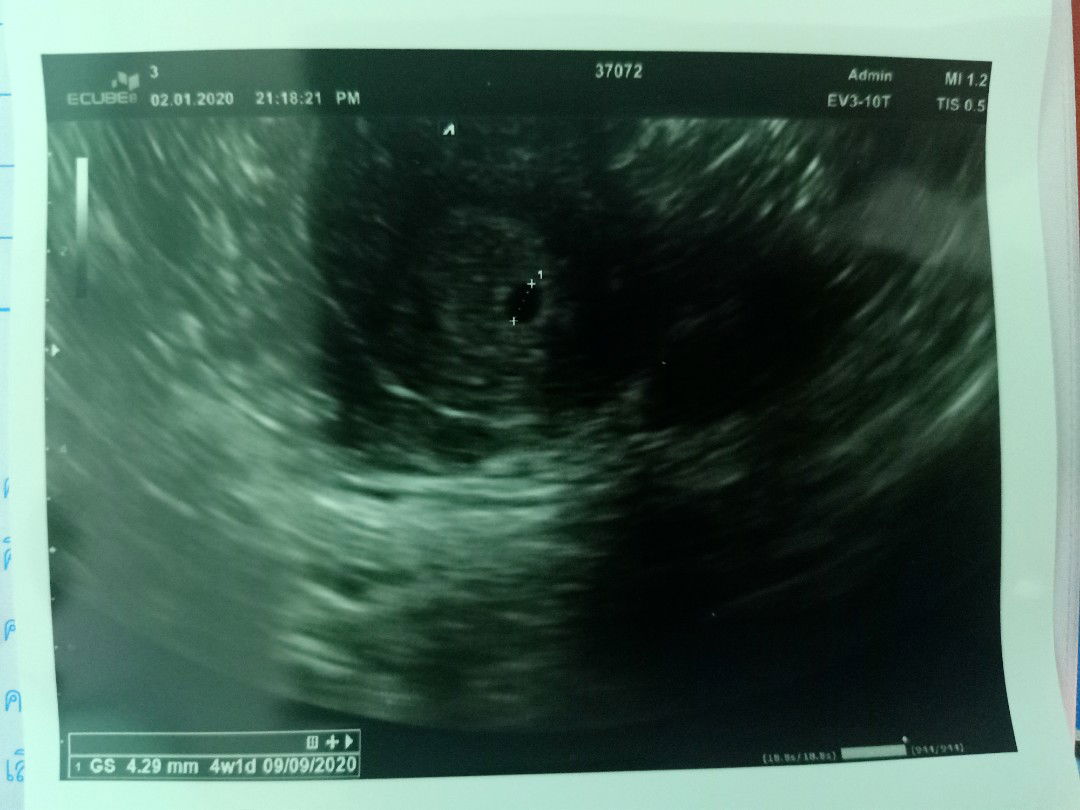

วันนี้ไปซาวด์ครั้งแรก เจอแต่ถุงตั้งภรรค์ค่ะ เล็กมากเลยค่ะ คุณหมอบอก รู้สึกกังวลมากเลยค่ะ? #4W1D ตามที่เครื่องบอกจะจริงมั้ยค่ะ